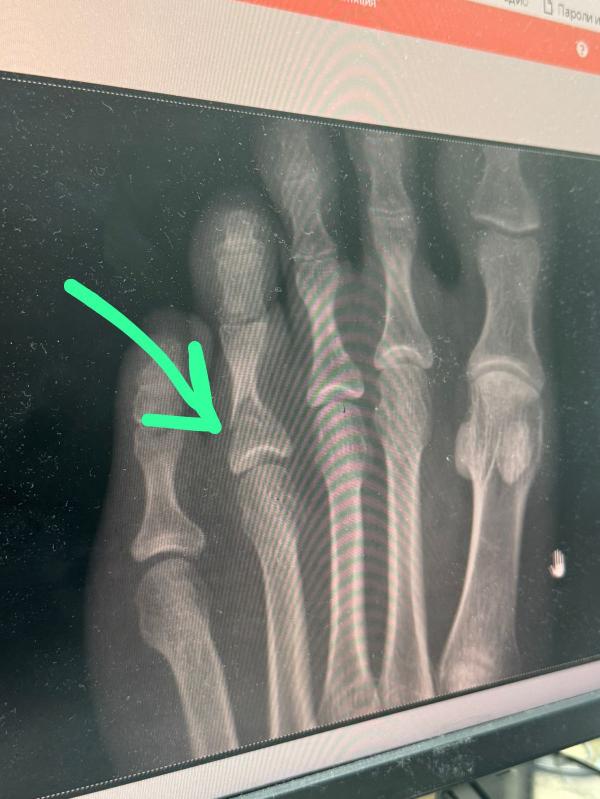

Сломала палец на ноге при украшении комнаты шарами

Украшала комнату шарами на др ребенка, упала сломала палец на ноге! Бинго 🤣